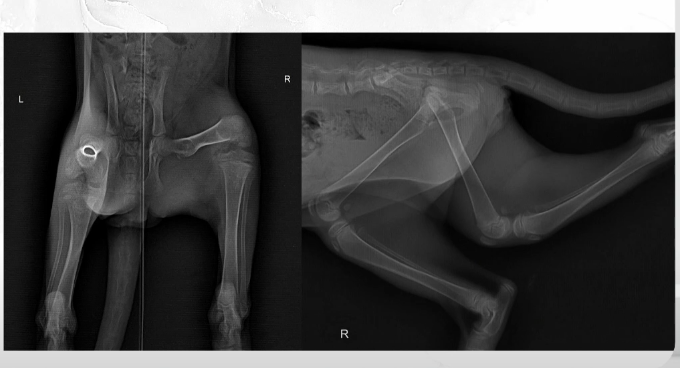

На снимке специалист заметила системное снижение плотности костных структур. Скелет выглядел менее крепким, чем должен быть у животного такого возраста. Также возникло подозрение на сужение таза, рассказала ветеринарный врач-диетолог Дарья Маслакова из сети ветклиник «Белый клык».

Бедренные кости, коленные и скакательные суставы, а также кости плюсны не демонстрировали значимых патологий.

Такая картина характерна для вторичного алиментарного гиперпаратиреоза — заболевания, возникающего из-за длительного нарушения баланса питательных веществ.

Пример вторичного алиментарного гиперпаратиреоза у котенка 3 месяца. Фото: скриншот из презентации Дарьи Маслаковой.

• Результат — скелет котенка на рентгене выглядит почти прозрачным.

Особенно коварна эта ситуация потому, что уровень кальция в анализах крови может долгое время оставаться нормальным. Организм поддерживает его за счет разрушения костной ткани, и проблему можно увидеть только на рентгенологических снимках.